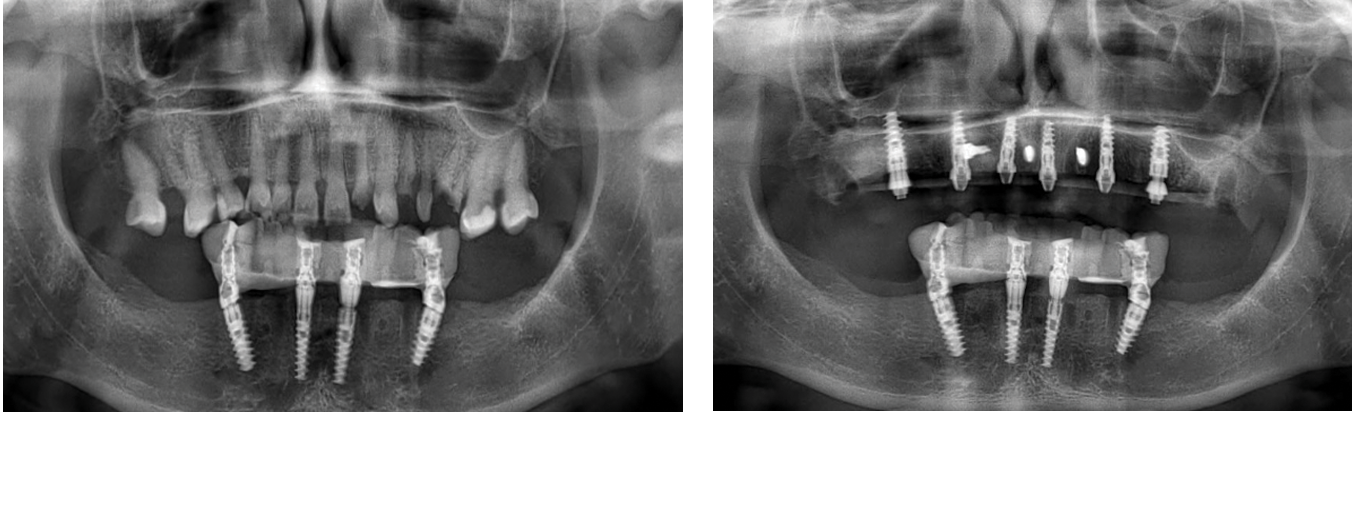

Join an elite group of clinicians for a 3-day immersive program where you’ll treat 3 full arch patients using state-of-the-art techniques: free-hand, guided surgery (flapless), and stackable guides with bone reduction.

Join a small group of experienced clinicians for an intensive hands-on program where you’ll place 15+ implants on real patients under expert supervision.

Train in both free-hand and guided techniques while mastering diagnosis, planning, bone biology, and soft tissue management.